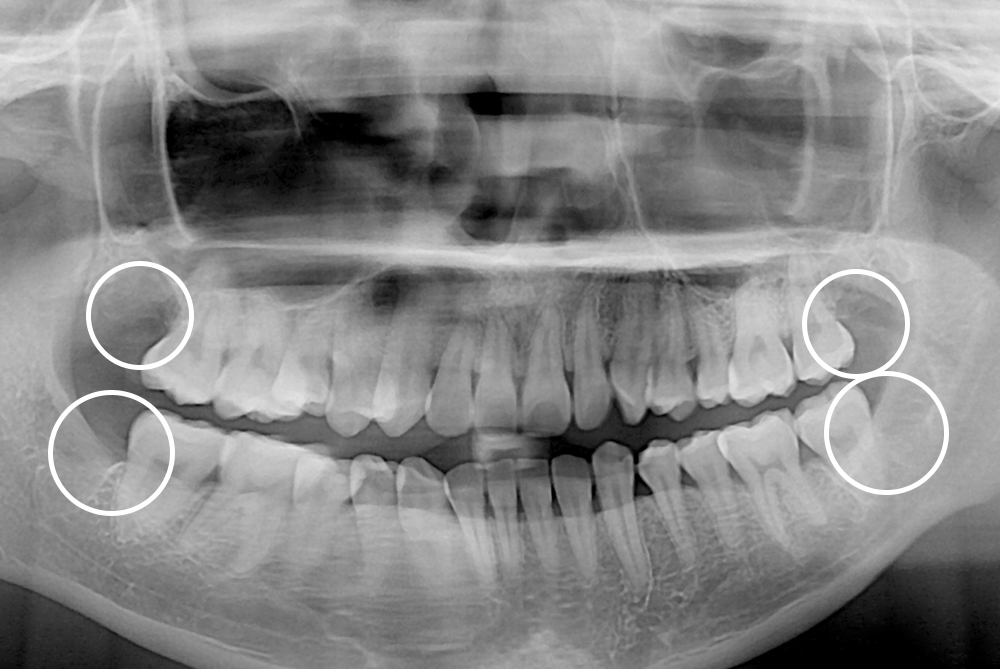

[사랑니] 매복 사랑니 발치

치료전 : 2018-05-16